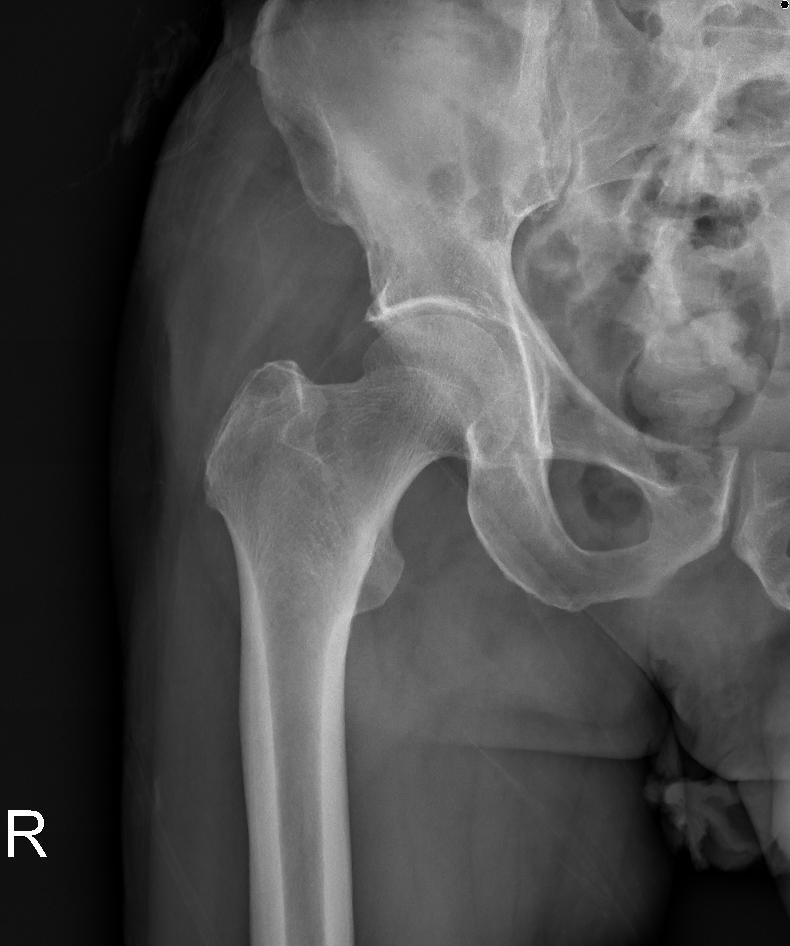

X-레이: 고관절의 변화를 보여주며, 골괴사의 초기 단계에서는 정상으로 나타날 수 있습니다.

자기공명영상(MRI): 골괴사증의 초기 단계를 포함하여 질환의 진행 상태를 가장 정확하게 평가할 수 있는 방법입니다.

컴퓨터 단층촬영(CT) 스캔: 뼈의 구조와 골괴사 영역의 정확한 크기 및 위치를 평가하는 데 도움을 줍니다.